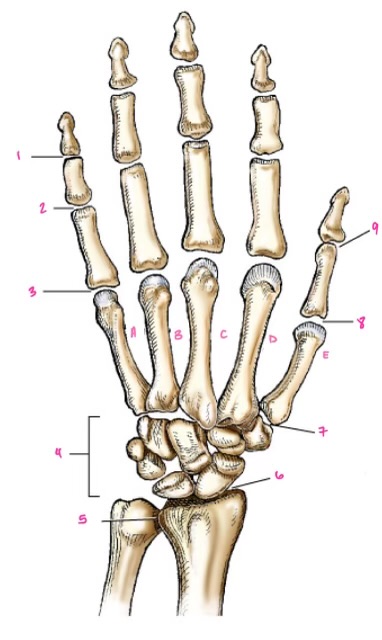

1

1

Hamate

2

2

Capitate

3

3

pisiform

4

9

Trapezoid

5

10

Trapezium

6

11

Scaphoid

7

14

Lunate

8

15

Triquetrum

9

16

Pisiform

10

17

Capitate

11

18

Hamate

1

Distal interphalangeal

13

2

Proximal Interphalangeal

14

3

Metacarpophalangeal

15

4

Intercapals

16

5

Distal radioulnar

17

6

Radiocarpal

18

7

Carpometacarpals

19

8

Metacarpophalangeal

20

9

Interphalangeal

7

Trapezoid

22

8

Trapzium

23

9

Capitate

24

10

Scaphoid

25

11

Lunate

26

13

Carpus

27

14

Triquetrul

28

15

Hamate

29

16

Metacarpus

30

17

Phalanxes